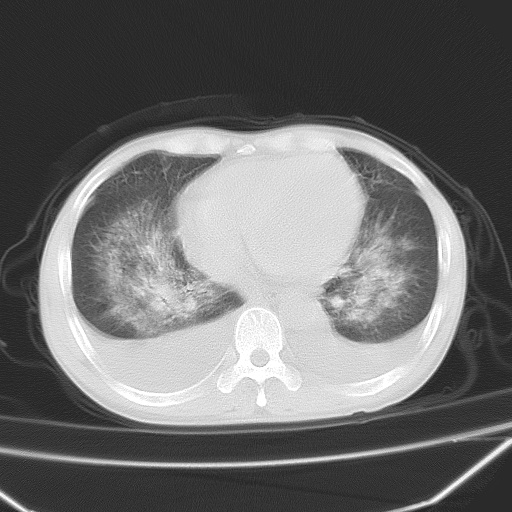

男、42岁、咯血3天。既往有甲亢、贫血、血尿蛋白尿史多年。血象:wbc:6.   中性粒:70.6%。

双肺堆成磨玻璃影,双测胸腔积液。考虑:肺水肿、间质性肺炎、真菌感染、ards、hiv感染、肺出血。

双肺野对称性磨玻璃影,分布于内中带,双侧胸水,患者有咯血。

1、间质性肺水肿;2、结合临床病史及实验室检查,考虑为肺出血肾炎综合征。    此病需与间质性炎症、粟粒性肺结核鉴别。

肺出血-肾炎综合征又称good-pasture综合征,属少见病,近几年国内有散在报告。此病原因未明,目前多数学者认为与自身免疫有关,即病人体内存在抗-gbm抗体,而病人肺毛细血管基底膜与肾小球基底膜有交叉反应性抗原,从而引起肺泡毛细血管基底膜和肾小球基底膜病变,导致肺出血及肾炎表现。血清抗-gbm抗体阳性,或组织活检见沿肾小球和肺泡基底膜有igg沉积,为本病的3个诊断依据。临床上有许多疾病同时表现为肺出血和肾炎,如系统性红斑狼疮、韦格肉芽肿和增殖性肾小球肾炎等,但这些疾病都不同时具备上述三方面的条件

双肺野广泛对称性磨玻璃影、实变影,以肺门为中心,主要分布于内中带,符合典型肺泡性肺水肿;伴双侧胸腔少量游离积液。结合患者既往病史且咯血就诊,支持多因素(尿毒症等)所致之肺水肿、肺出血、胸水;影像表现暂不考虑心源性水肿,且症状也不太符。需密切随诊结合临床治疗等进一步明确。

心影增大密度略低,双肺磨玻璃样高密度影及双侧胸腔积液,考虑心功能不全继发双肺肺水肿及双侧胸腔积液。心影密度略低,考虑贫血所致。